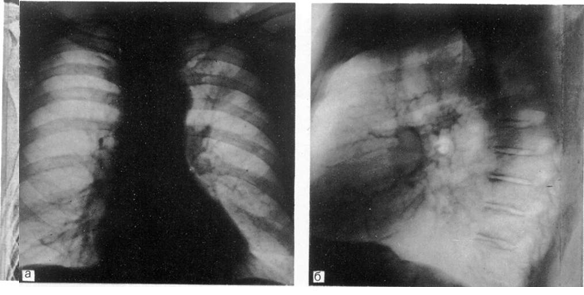

Рис. 3. Рак верхней доли левого легкого.

а — прямая рентгенограмма: б — боковая рентгенограмма.

Последующее рентгенографическое обследование должно углублять и расширять представления о характере изменений в легких и грудной полости. Эти исследования проводят в прямой (переднезадней) и боковой проекциях, дополняя их при необходимости снимками в косых проекциях и прицельными рентгенограммами (рис. 1). Важным достоинством рентгенографии являются объективность и достоверность полученных результатов, возможность сопоставления с данными ранее проведенных рентгенографических обследований, т. е. возможность динамического наблюдения. Последнее нередко является одним из важнейших факторов для установления правильного диагноза.

Рентгенографическое обследование в двух проекциях позволяет с наибольшей точностью определить локализацию и распространенность поражения легких, изменения в средостении, состояние междолевых щелей, оценка и сопоставление степени прозрачности участков легкого в различных его отделах, мельчайшие очаговые тени, что особенно ценно при проведении дифференциального диагноза между туберкулезом легких, саркоидозом, пневмокониозом и другими заболеваниями, дающими исходные рентгенологические изменения.